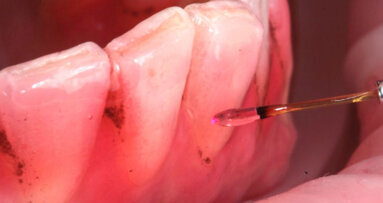

La prima paziente è una donna di anni 33 che gode di buona salute generale, non assume farmaci e non è una fumatrice. All’esame obiettivo si notano diverse otturazioni in amalgama, corone protesiche e un impianto osteointegrato ma non emergono problemi particolari, eccetto delle black stains di cui la paziente lamenta la presenza. Si procede con la raccolta della documentazione fotografica, la rilevazione dell’indice di placca attraverso l’utilizzo del rivelatore di placca e la compilazione della cartella parodontale. Dall’analisi dei dati raccolti non emergono problematiche parodontali, ma è da notare quanto l’igiene domiciliare sia insufficiente (IP=69%). Vengono raccolti in una tabella riassuntiva anche i dati relativi alla presenza di black stains. Si prosegue con la motivazione e l’istruzione ad un’accurata igiene orale domiciliare e si invita la paziente a tornare una decina di giorni dopo per sottoporsi ad una seduta di igiene orale professionale. La paziente ha dimostrato una buona adherence rispetto ai consigli di igiene che le sono stati dati, il livello di igiene orale è notevolmente migliorato e si decide per un richiamo di igiene semestrale. Dopo aver effettuato la seduta di igiene professionale si chiede alla paziente di cambiare testina allo spazzolino elettrico in uso e di assumere “Lautoselle” una volta al giorno per i tre mesi successivi. La paziente viene controllata dopo un mese e quindi al termine del periodo di assunzione del probiotico, vengono nuovamente scattate delle fotografie e compilata la tabella riassuntiva per monitorare la formazione delle black stains. Infine, lo stesso tipo di controllo viene effettuato dopo altri tre mesi, cioè a distanza di sei mesi dalla seduta di igiene orale e quindi dalla rimozione delle black stains; successivamente è stata effettuata la seduta di mantenimento di igiene.

A distanza di sei mesi dalla rimozione dei pigmenti durante la seduta di igiene orale professionale, i siti che presentano black stains sono diminuiti del 53,13%. I pigmenti inoltre hanno iniziato a ripresentarsi, seppur in quantità ridotte, a due mesi dalla seduta di igiene, mentre solitamente la ricomparsa avveniva a distanza di 3-4 settimane (Figg. 4a-4c).

Fig. 4a - Fotografia del secondo sestante palatale al primo rilevo delle black stains.